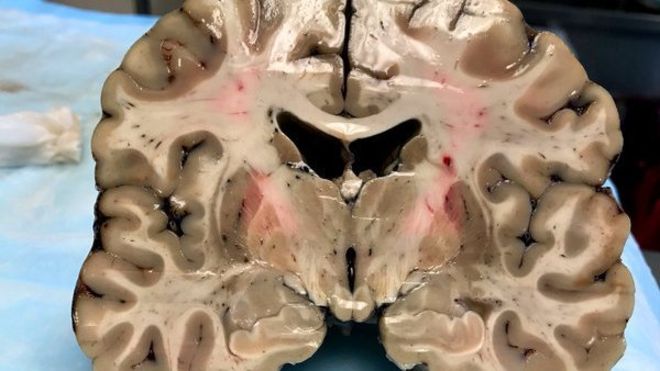

A pesar de su apariencia saludable exterior, el cerebro estaba dañado por encefalopatía traumática crónica.(Foto: B. University)

Colocado sobre una mesa de laboratorio, horas después de su muerte, el cerebro de Aaron Hernández ofrecía una apariencia saludable.

Pero lo que en principio parecía un cerebro sano, escondía debajo de su superficie un secreto que sorprendió a los científicos que llevaron a cabo la autopsia del jugador.

El órgano mostró un estado de encefalopatía traumática crónica (CTE, por sus siglas en inglés) similar al de alguien afectado por esa enfermedad cerebral degenerativa de 60 años.

Al cortarlo en pedazos de 1,3 centímetros, los investigadores notaron la existencia de "cuevas" de un tamaño inusual en el centro del órgano, que se expandían a medida que el tejido cerebral disminuía.

Según Caramelli, se trata de algo poco común para una persona de 27 años, edad en la que el cerebro suele ocupar casi todo el cráneo.

El equipo de McKee también observó que el septo pelúcido, una membrana que divide los dos lados del cerebro, estaba perforada, situación que suele ocurrir con los pacientes que padecen CTE.